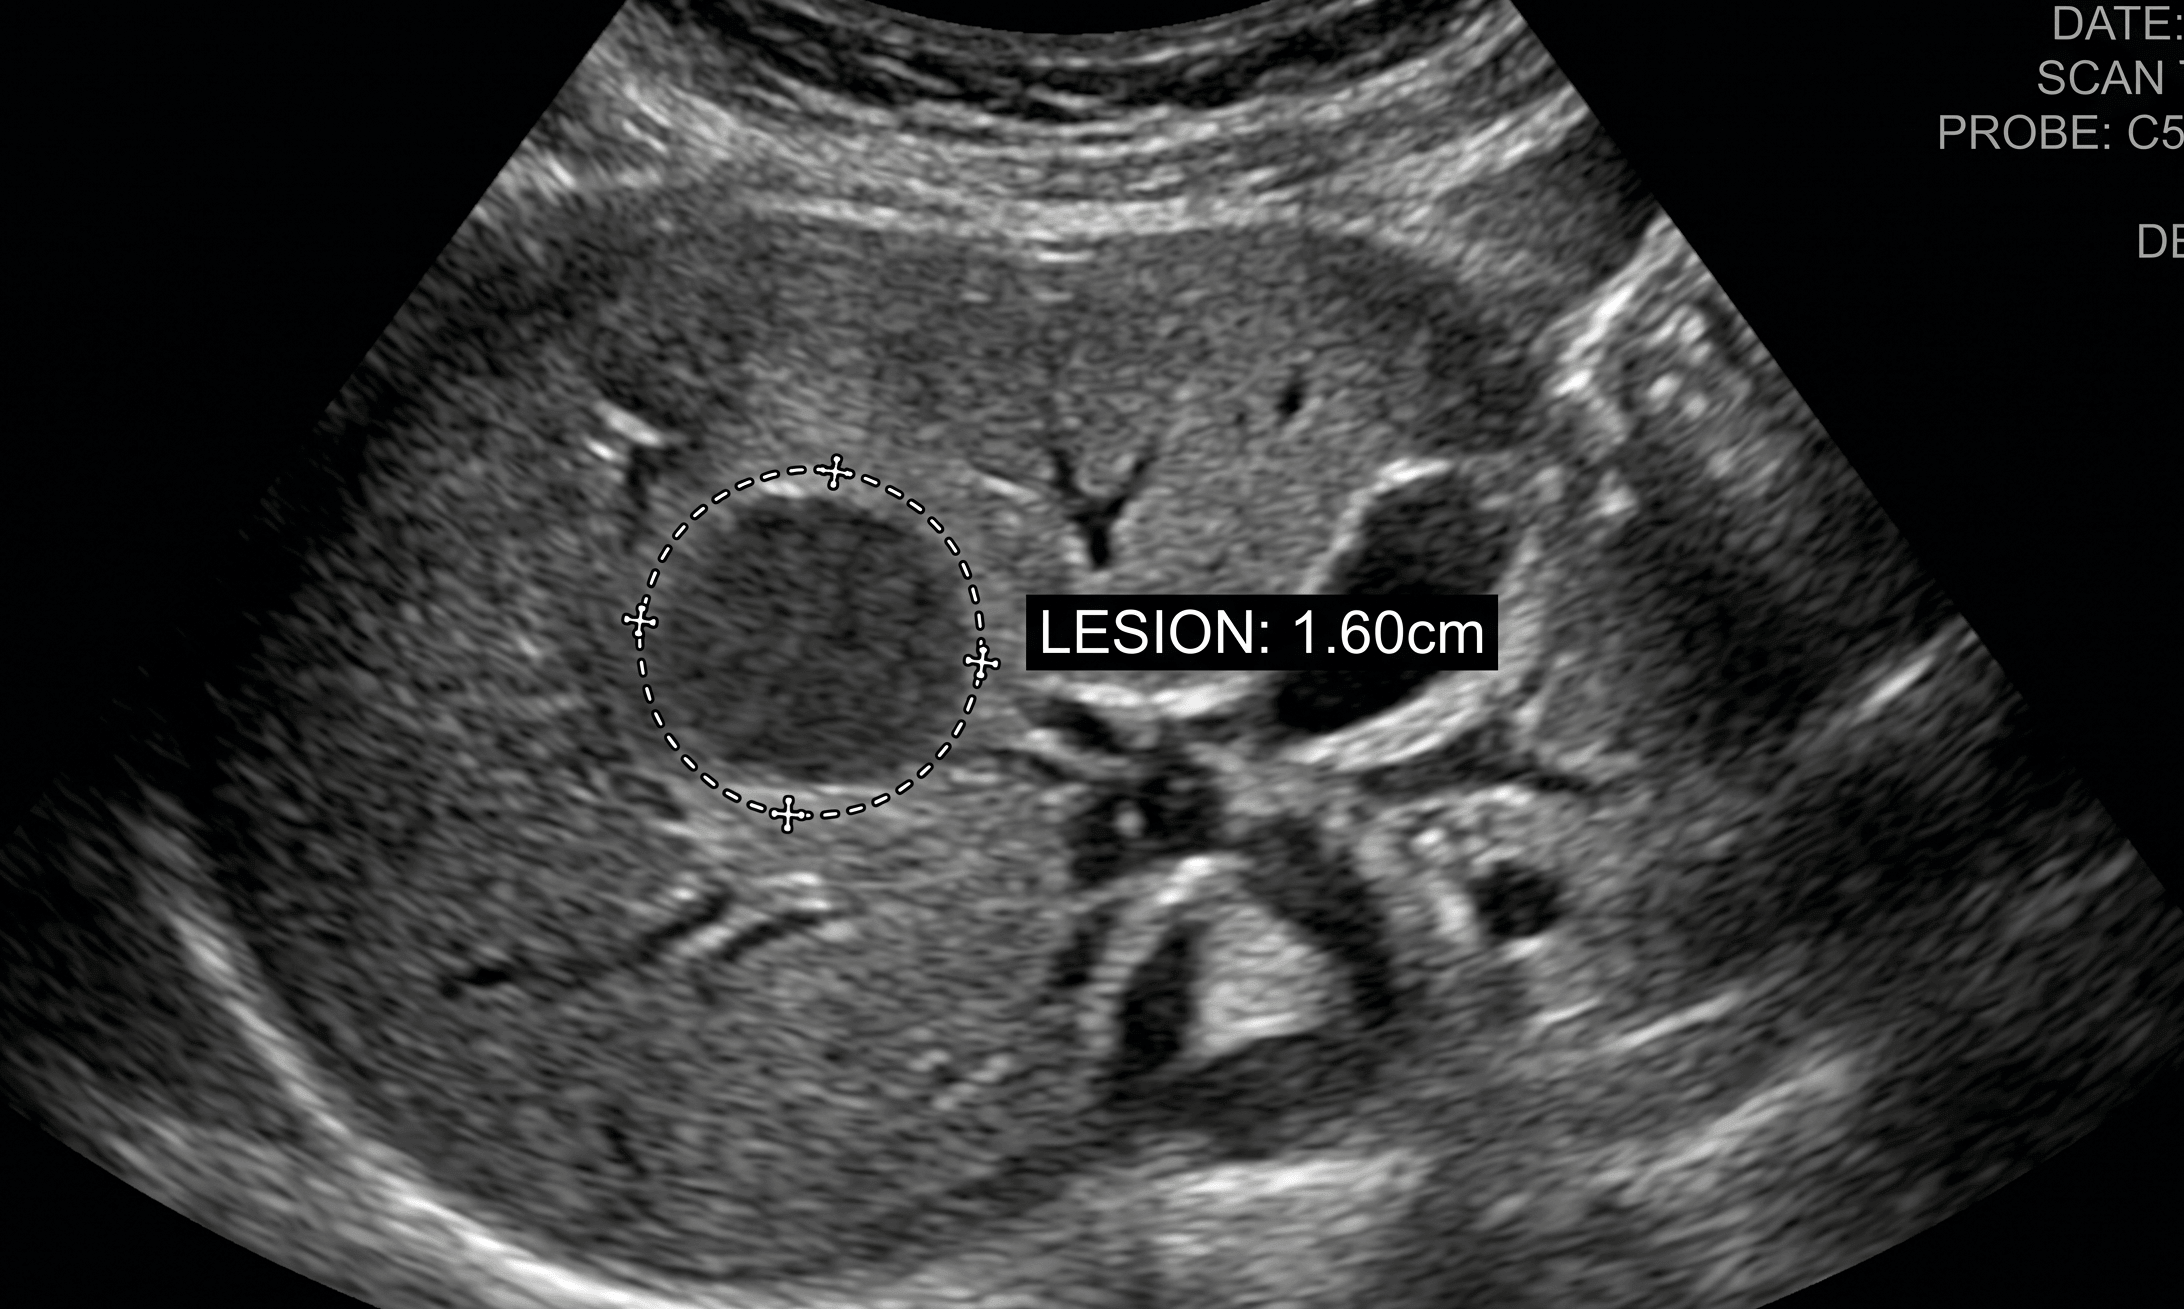

건강검진을 하다가 간에 1.6cm 정도의 병변이 발견되었다. 정밀 복부 CT를 해보라는 소견이었는데, 별다른 증상이 없어서 미루다가 진단받고 6개월 만에 병원에 방문하였던 후기를 알려드리려고 합니다. 일이 바쁘고, 병원 갈 시간이 없다는 핑계를 대긴 했지만 무척 걱정스러웠던 6개월이었습니다. 혹시라도 저와 같은 증상을 겪고 있는 분 계시다면 참고하세요.

간병변 1.6cm 진단 초음파